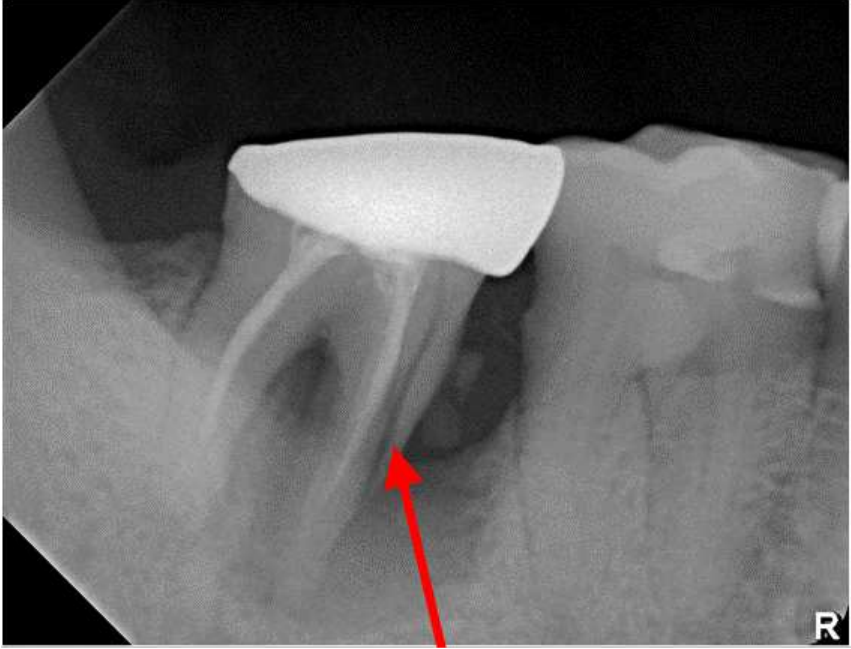

68.下圖紅色箭頭指示處之牙齒病變,其最可能之診斷為何?

(A)Dilaceration of root (B)Fusion of root (C)Concrescence of root (D)Fracture of root